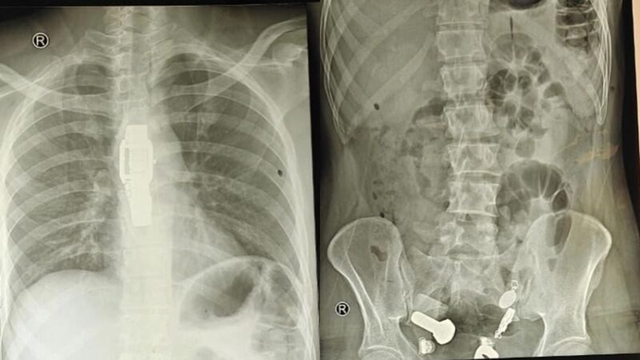

Một người đàn ông ở Ấn Độ gần đây đã nhập viện vì đau dạ dày dữ dội, khiến anh ta khó ăn. Ban đầu, các bác sĩ nghi ngờ đây chỉ là một vấn đề tiêu hóa đơn giản, nhưng kết quả chụp X-quang cho thấy một vật thể lạ bên trong cơ thể anh ta.

Sau khi thăm khám và chụp X-quang, các bác sĩ thấy một chiếc đồng hồ đeo tay, bu lông và ốc vít, được gắn chặt vào nhau... trong bụng bệnh nhân.